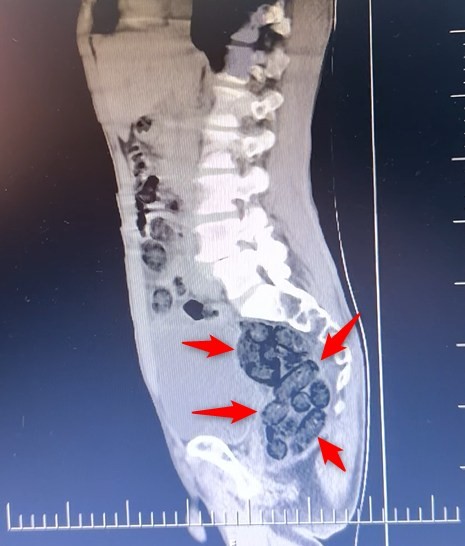

Şüpheli hareketler sergileyen yabancı uyruklu bir yolcunun yapılan tıbbi kontrollerinde, midesinde kapsüllenmiş halde 64 parça uyuşturucu madde olduğu belirlendi.

Toplamda 472 gram metamfetamin yutarak sevkiyat yapmaya çalışan şahıs, midesindeki paketlerin çıkarılmasının ardından gözaltına alındı.